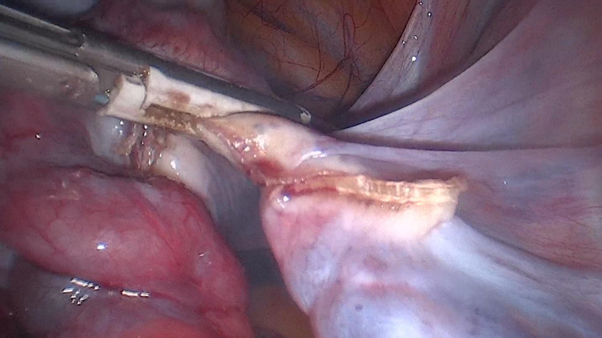

Intraoperative images

1. The right ureter is located and the right infundibulopelvic ligament is sectioned with advanced bipolar energy.

1. Right salpingo-oophorectomy is performed.

1. There is evidence of a twist in the ipsilateral tube.